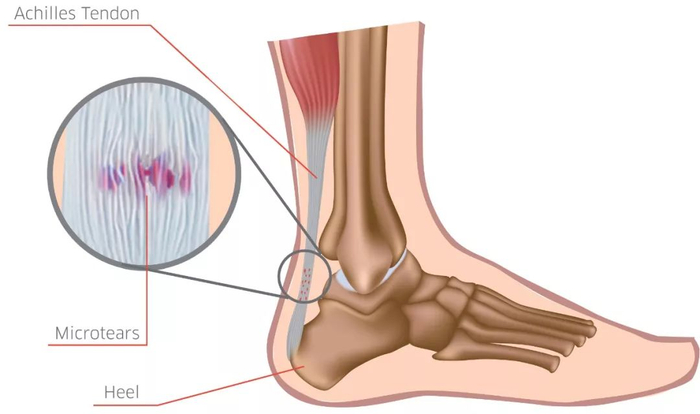

跟腱的过度使用,通常会造成超过生理极限的超负荷作用于跟腱,从而使跟腱出现细微损伤。

开始时,这些细微损伤并不会造成明显不适。但出现损伤后的跟腱血液供应会逐渐变差,延长恢复时间,当再次训练时又会造成二次伤害,最终转变成严重损伤。其实这个过程和铁锈侵蚀整块铁非常像,开始并不起眼,但逐渐积累起来,最终却会引发断裂等情况。